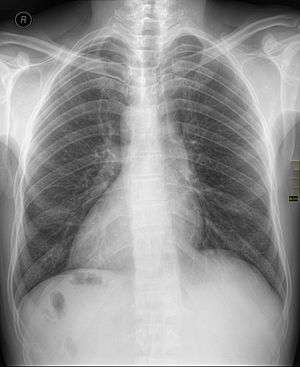

| Chest X ray of a person with dextrocardia situs inversus showing the cardiac apex facing the right | |

Dextrocardia (from Latin dexter, meaning "right," and Greek kardia, meaning "heart") is a rare congenital defect in which the apex of the heart is located on the right side of the body.[1] There are two main types of dextrocardia: dextrocardia of embryonic arrest (also known as isolated dextrocardia) and dextrocardia situs inversus. Dextrocardia situs inversus is further divided.

Dextrocardia situs inversus refers to the heart being a mirror image situated on the right side. For all visceral organs to be mirrored, the correct term is dextrocardia situs inversus totalis.